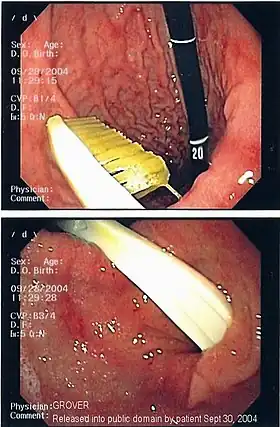

| An endoscopy image of the stomach, showing a foreign body in the form of a toothbrush. | |